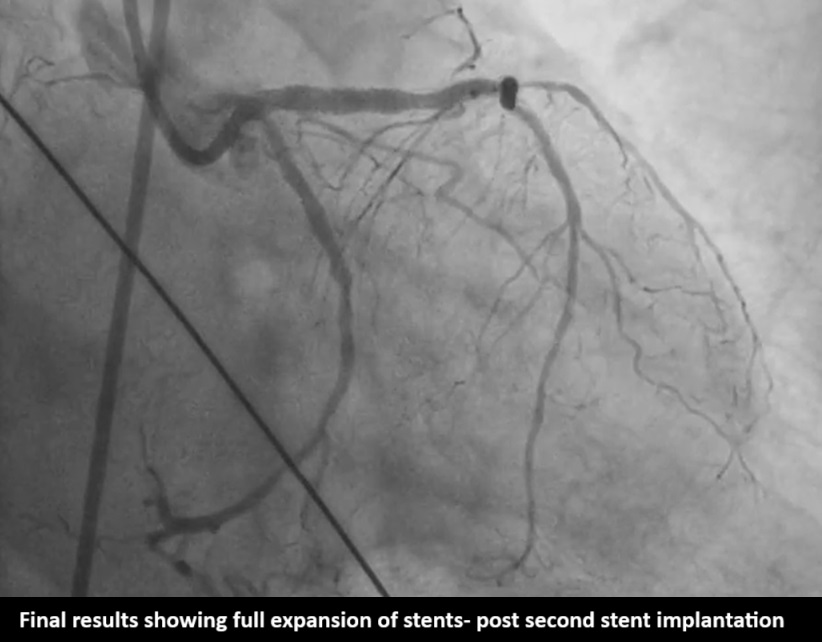

Pre PCI-IVUS showedsuperficial calcium 360 degree at ostium, Predilation was done with 2.5mm OPNballoon and 2.5 wolverine balloon, and 3.5x23mm (Xience Prime company) stentwas deployed at 18atm still there was severe dog boning and Crumpled stent canbe seen in Philips Sync Vision. 3.5x12 IVL done (shockwave company) with 8shocks each of 10 cycles within the crumpled portion Note inner dots containthe region of crumpled stent the way to position IVL for maximum strength. Post-inflationwith IVL, Stent fracture happened and a Clot started forming, another 3.5x23mm (BostonScientific Company) stent deployed in LAD with good result. After 2 hours inCCU patient suddenly developed chest pain and LVF, almost collapsed with BP40/20. Patient was started on inotropes, NIV support and ECG showed new onsetLbbb. It was thought that it could be SAT Gave additional heparin, Started onGp2 B. Fresh echo showed Rwma in LCX territory, new development. Put on IABP andShifted to Cathlab and a check angio done, Final angio with flowing LCX and LADPatient slowly weaned off NIV and IABP in further 3 days